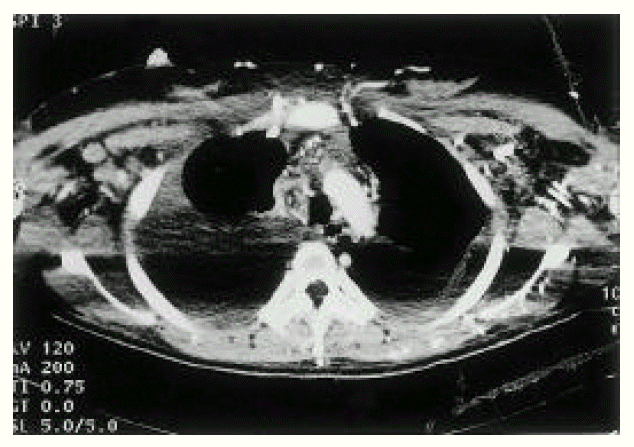

An X-ray film of the chest showed bilateral pleural effusion. Computed tomographic (CT) scan of the thorax (Fig. 3) demonstrated large amounts of bilateral pleural effusion and SVC occlusion with prominent collateral vessels at the chest wall, both axillary areas and within the mediastinum. Abdominal CT (Fig. 4) showed ascites and obliterated IVC, except for the short segment near the heart. Also, many collateral vessels were noted in the splenic hilar area, hepatosplenic ligament, retroperitoneum, mesentery, both perihilar areas of kidney, both paravertebral areas, perirectal area and the whole abdominal wall. Multiple round and wedge shaped, non-enhancing hypodense lesions suggest multiple liver infarction and diffuse hepatomegaly and mild splenomegaly were noted.

Fig. 3.

CT of chest. SVC and brachiocephalic veins are obliterated (arrow) and multiple collateral vessels are opacified at anterior chest wall and both axilla.